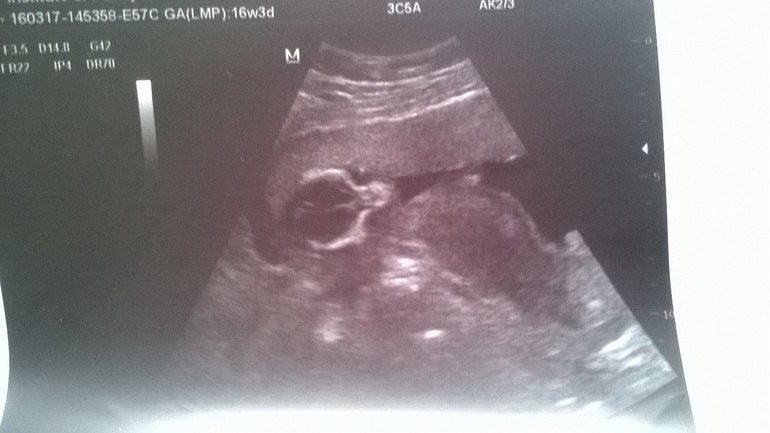

Еще и по записывал параметры не понятные для меня и фото в котором я вообще нифига не пойму.

Короче девчонки посмотрите, может кто поможет расшифровать и узд и фото)

А на узи скорее всего головка- вид сверху (черепная коробка) и пузико)) у меня почти такое же сть фото.. Там мне пояснил врач где что.. Про пол предположили на первом скрининге и на 15 неделе подтвердили.. Это все индивидуально, ребенок может располагаться как угодно и удобно для него..